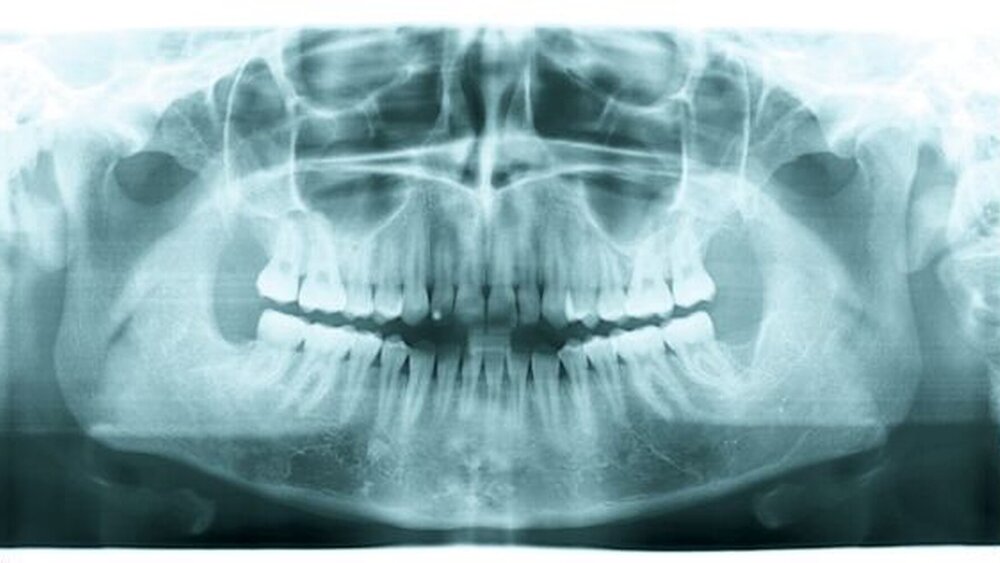

Eine 18-jährige, ansonsten gesunde, weibliche Patientin wurde zur weiteren Abklärung zweier in einer Panoramaschichtaufnahme als Zufallsbefund erkannter Osteolysen im Unterkieferseitenzahnbereich beidseits vorstellig (Abbildung 1). Die klinische Untersuchung der Patientin zeigte vitale, nicht gelockerte Zähne in allen vier Quadranten sowie keine Beeinträchtigung des Nervus alveolaris inferior beidseits.

In der Panoramaschichtaufnahme präsentierte sich eine scharf begrenzte, beinahe symmetrische Osteolyse im Seitenzahnbereich des linken und des rechten Unterkiefers ohne Verdrängung der Nervkanäle. Auch konnte keine Resorption oder Verdrängung der Zahnwurzeln, die partiell in die osteolytischen Areale hereinragten, beobachtet werden.